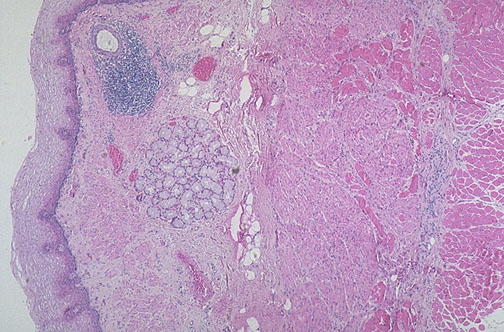

| Normal non-keratinizing esophageal squamous mucosa is seen here at the left, and there is underlying submucosa containing mucus glands, with a duct surrounded by lymphoid tissue. At the right is the muscularis with smooth muscle as well as outer skeletal muscle. |